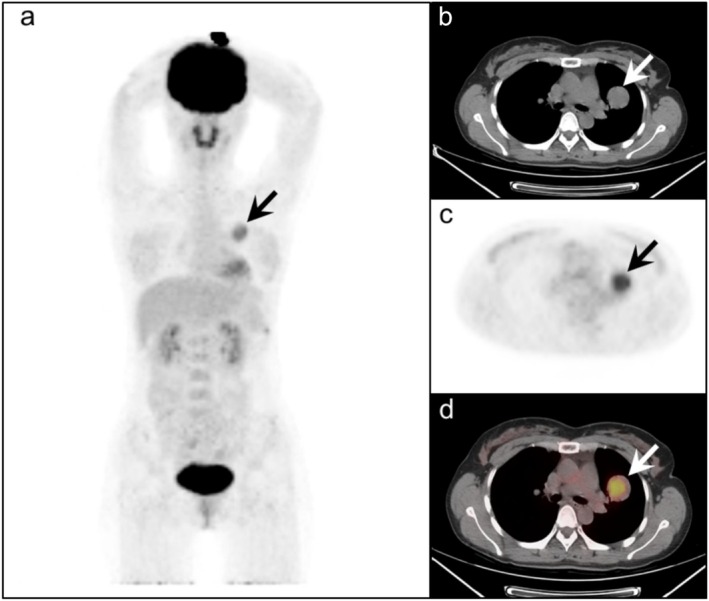

Results: The 46 tumors were randomly distributed in each lobe of both lungs. The mean maximum diameter of these lesions was 2.2 cm (range: 0.6 to 6.5 cm). The mean SUVmax was 2.96 ± 1.88 (median: 2.69, range: 0-9.02). Thirty-three cases were categorized as mild to moderate FDG uptake, eleven cases were categorized as intense FDG uptake, and no FDG uptake was observed in the remaining two cases of the lesions qualitatively evaluated. The SUVmax of the PSP showed a positive correlation with the maximum diameter of the tumors (R = 0.493, R2 = 0.258, and p < 0.001). SUVmean (R = 0.500, R2 = 0.259, p < 0.001), SUVpeak (R = 0.553, R2 = 0.324, p < 0.001), MTV (R = 0.773, R2 = 0.592, p < 0.001) and TLG (R = 0.800, R2 = 0.654, p < 0.001) were positively correlated with the maximum diameter of the tumor.

Conclusion: In our study, statistically significant positive correlations were found between SUVmax, SUVmean, SUVpeak, MTV, and TLG and the maximum diameter of PSP. We found that the maximum diameter of the tumor is associated with an increase in FDG uptake in PSP, reflecting a potential correlation between lesion diameter and PET metabolic parameters, indicating a link between structural features and metabolic activity.